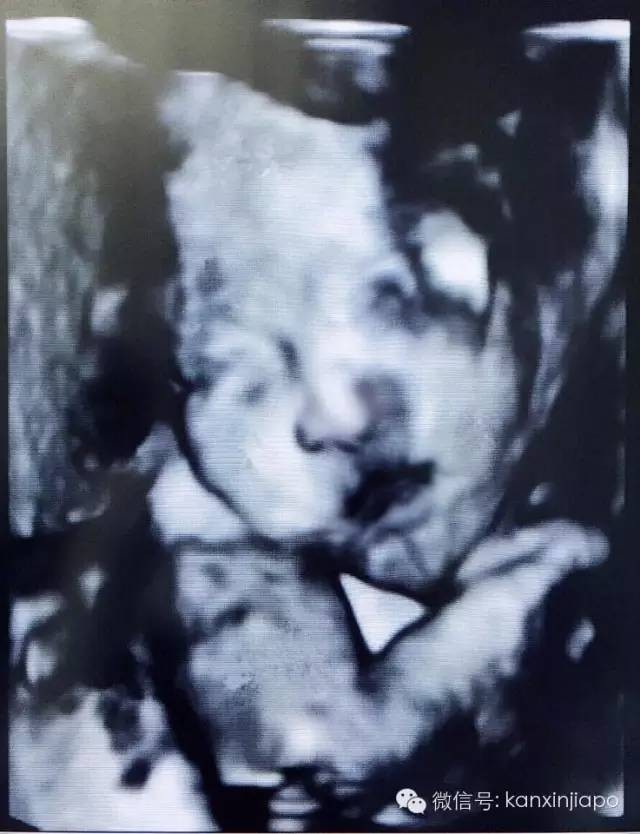

小V宝出生前的“照片”: